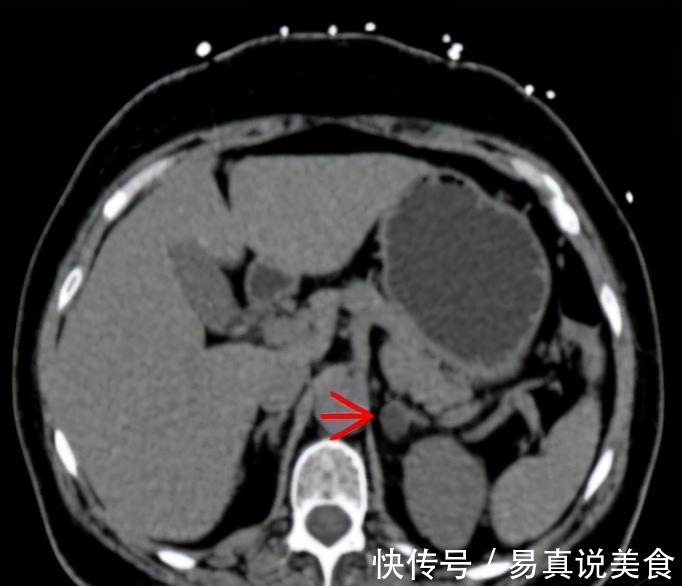

62岁的孙阿姨是一名“资深”高血压患者,已与高血压“斗智斗勇”20多年。这么多年来,孙阿姨的降压药换了又换,血压却一直高居不下。今年年初,孙阿姨血压一度高达190/120mmHg,在家人的陪伴下,来到郑州中心医院接受系统治疗。高血压科余淑华主任接诊后,为孙阿姨安排了CT 检查,结果发现了左侧肾上腺腺瘤,进一步介入检查后,孙阿姨被确诊为原发性醛固酮增多症,由左侧醛固酮瘤引起。

图源:郑州中心医院余主任表示,原发性醛固酮增多症引起的高血压,单靠吃降压药的作用不大,必须手术切除。随后,孙阿姨转入泌尿外科,接受了腹腔镜下左肾上腺切除术。术后孙阿姨没有服用任何降压药物,血压降到了133/66mmHg,一直很稳定。一、4种高血压,无需吃药一般来说,高血压患者要长期服药,不能断药,否则可能出现并发症。但北京医院心血管内科汪芳主任介绍,其实高血压的类型有很多,并不是所有患者都要吃药。以下几种特殊的高血压类型,就不用吃药。1、原发性醛固酮增多症正常情况下,人体会分泌少量醛固酮,一旦分泌过量,就会导致水钠潴留,血容量增多,引起原发性醛固酮增多症,表现为高血压和低血钾。据统计,我国约4?初诊高血压患者由原发性醛固酮增多症引起,对于此类高血压,应积极治疗原发病,服用降压药的效果不大。如果不能手术,可以服用螺内酯、依普利酮等药物进行治疗。